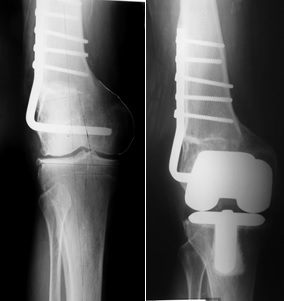

Figura 1: a) Paciente de 70 años, con genu valgo artrósico derecho y antecedente de osteotomía varizante femoral. Desalineación coronal femoral de 8° en varo y eje anatómico de 13° de valgo. Observar la limitación para el empleo de la guía femoral endomedular por la deformación y la osteosíntesis. b) ATR con eje final de 3° de valgo. Se empleó guía de corte femoral extramedular. La prótesis femoral queda centrada en la epífisis y parece ¨descentrada¨ respecto de la diáfisis.